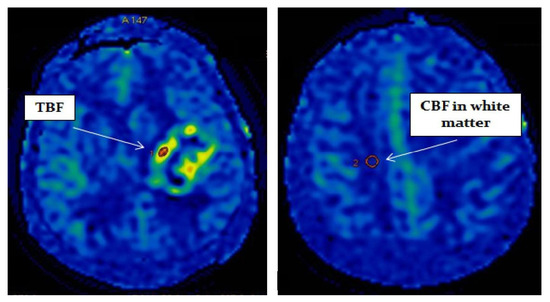

Postprocessing of the obtained data was performed using the ReadyView software package (GE Healthcare). To measure blood flow in the tumor, a region of interest (ROI) with an area of 20 mm2 ± 10 mm2 was designated in the zone with the highest CBF value (determined on color blood flow maps). In the designated ROI, the average value of TBF was calculated. To eliminate individual blood flow differences, we normalized TBF (nTBF) to blood flow in the intact white matter of the contralateral hemisphere semioval center. For this purpose, ROI with the same area (20 mm2 ± 10 mm2) as the tumor ROI was placed—Figure 1. To obtain normalized values, the obtained TBF data were divided by the blood flow in the semioval center (nTBF = maxTBF/CBF of the intact white matter of the contralateral hemisphere semioval center).

Figure 1.

Blood flow measurement on parametric maps.